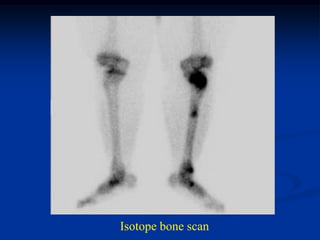

Case #7               Jan 6   Feb 2

Adult Intestinal

Osteomalacia

49 yr female with

severe obesity and

gastric bypass 2 yr

ago and now recent

gradual onset of

pain in leg without

trauma

Isotope bone scan

Cor T-1              T-2                Gad

Increased alkaline phosphatase and PTH levels

Sag T-1   T-2